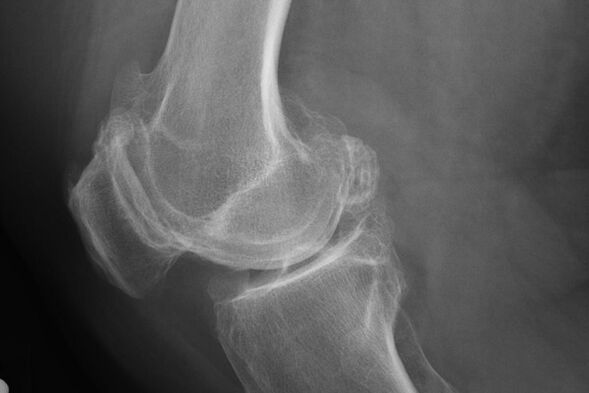

Qoida tariqasida, ushbu bosqichda kasallikning tashxisi tasodifan x-i karda paydo bo'ladi. Unda shifokor xaftaga oid ba'zi tartibsizliklarni qayd etishi mumkin. Shuningdek, bu yoritgichni qo'shma qismlari orasidagi toraytirish mumkin.

X--var xaftada og'ishlarni aniqlashga yordam beradi.

Tekshiruvdan so'ng shifokor bemorning rentgenografiyasini belgilaydi. Bu har qanday darajadagi tizza bo'g'imlarining asosiy usuli hisoblanadi.

X -Aray shifokorga bo'g'imning xaftaga kiradigan o'zgarishlar g'oyasi beradi. Biroq, ba'zi hollarda dastlabki bosqich rasmda aniqlanmasligi mumkin.

Agar kerak bo'lsa, shifokor rentgenogramma yoki hisoblangan va magnit rezonans tomografiyasining takroriy qismini buyurishi mumkin.